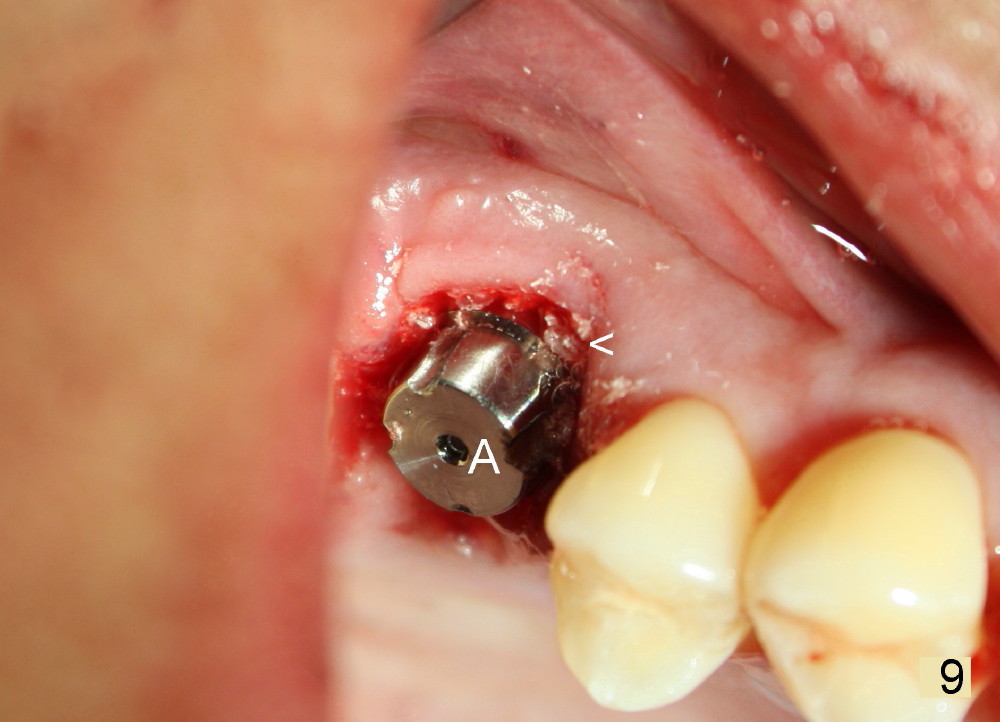

The tooth #3 has severe periodontitis with probably endodontic lesion (Fig.1,2). The patient is a 43-year-old man with apprehension of dentistry. An acute infection causes pain and tooth shift (Fig.4,5). A 7x17 mm immediate implant is planned (Fig.3). The palatal socket is shallow (Fig.6 P), corresponding to severe recessive palatal root (Fig.5 P). The osteotomy is created mainly in the buccal socket (Fig.6 B), exactly in the lingual slope of the septum. Initially osteotomes are used, followed by tap placement (Fig.7 T (4.5x20 mm at the depth of 17 mm). When the implant is placed as planned (Fig.8 I), there is more vertical contact (Fig.8 red line) than that associated with the tap (Fig.7 red line). The corresponding insertion torque is between 50 and 60 Ncm. There is only one small gap buccally, which is filled with bone graft (Fig.9 <). After the insertion of a short abutments with vertical slots (Fig.9,10 A), perio dressing is used to cover the wound. The palatal socket is expected to heal uneventfully (Fig.10 P). In fact, it does in 7 days (Fig.12 P); the bone graft in the mesiobuccal aspect is healing and stabilized (Fig.11 <). By two weeks postop, the mesiobuccal socket has healed (Fig.13 <). With removal of a diseased tooth, our body has amazing power to heal.